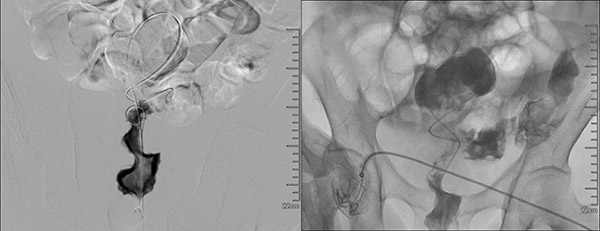

肿瘤介入科张申众主任带领团队,历时三十分钟,在DSA引导下,顺利完成结肠支架置入术。术中利用加硬导丝、导管穿越肠道扭曲狭窄段,确定狭窄部位及长度。选用10F的25mm×9cm的支架,沿着导丝插入支架至狭窄部位。肠道支架调整至合适位置后,在DSA引导下精准释放支架。当支架完整释放后,肠腔瞬间通畅,堵塞的粪便通过支架“喷涌而出”,患者严重的腹痛腹胀症状立刻得到缓解,生命通道被精准打通!

DSA下导丝穿越狭窄段